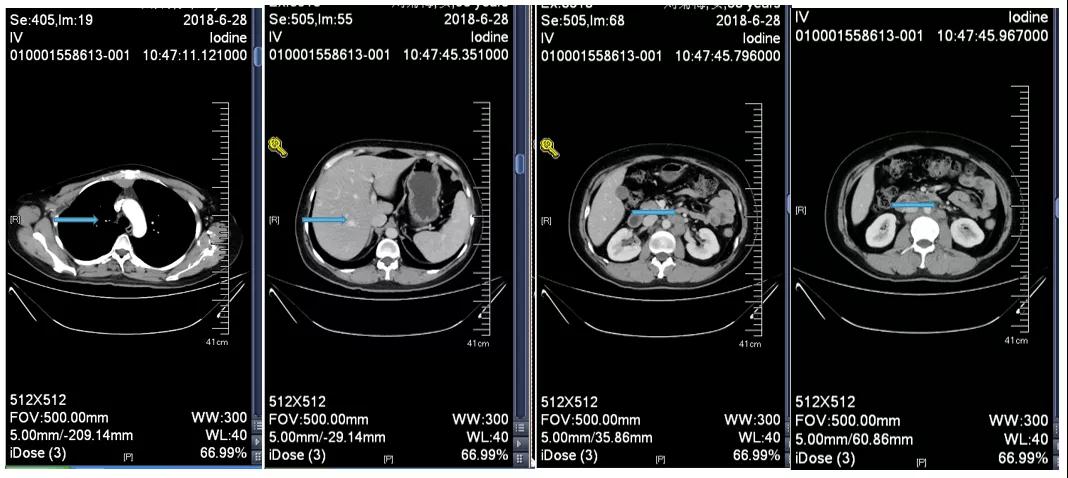

胸腹部增强CT示(2018-6-28):胸骨后占位,肝内异常强化灶,腹膜后肿大淋巴结。

2018-7-17成功入组ELAINA临床研究(试验方案编号:BO29919),IWRS分配随机号3210。于2018-7-17开始接受T-DM1 3.6mg/kg(252mg)治疗,并间断对其进行疗效评估。现阶段患者PFS达近40个月。

靶病灶:腹主动脉左侧和下腔静脉右侧淋巴结

非靶病灶:肝左叶、肝右前叶下段;纵膈胸骨后淋巴结节;前上纵膈淋巴结;腹膜后小淋巴结

影像学评估-纵膈淋巴结:

影像学评估-肝脏:

影像学评估-腹膜后淋巴结: